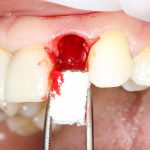

Ремарка: еще на этапе консультации с участием стоматолога-ортопеда, мы признали 44 зуб негодным и решили его удалить. Перед проведением разреза мы убрали коронку с 44 зуба и подготовили его к удалению. Так мы избежим попадания фрагментов коронки в открытую рану, а проведение самого разреза получится проще и аккуратнее.

За редким исключением, мы всегда проводим разрез в пределах прикрепленной десны. Даже если её участок шириной всего полтора-два миллиметра — постарайся оставить его в этих границах.

Поскольку мы планируем получать аутотрансплантат из этой же области, мы продляем разрез до донорской зоны. В этом участке удобно вывести его вестибулярно, прямо в проекции наружной косой линии.

Ну хорошо. Швы сняли. Делаем разрез. Обрати внимание, что после всех проведенных операций у нас остается очень небольшой по ширине слой жевательной слизистой оболочки: